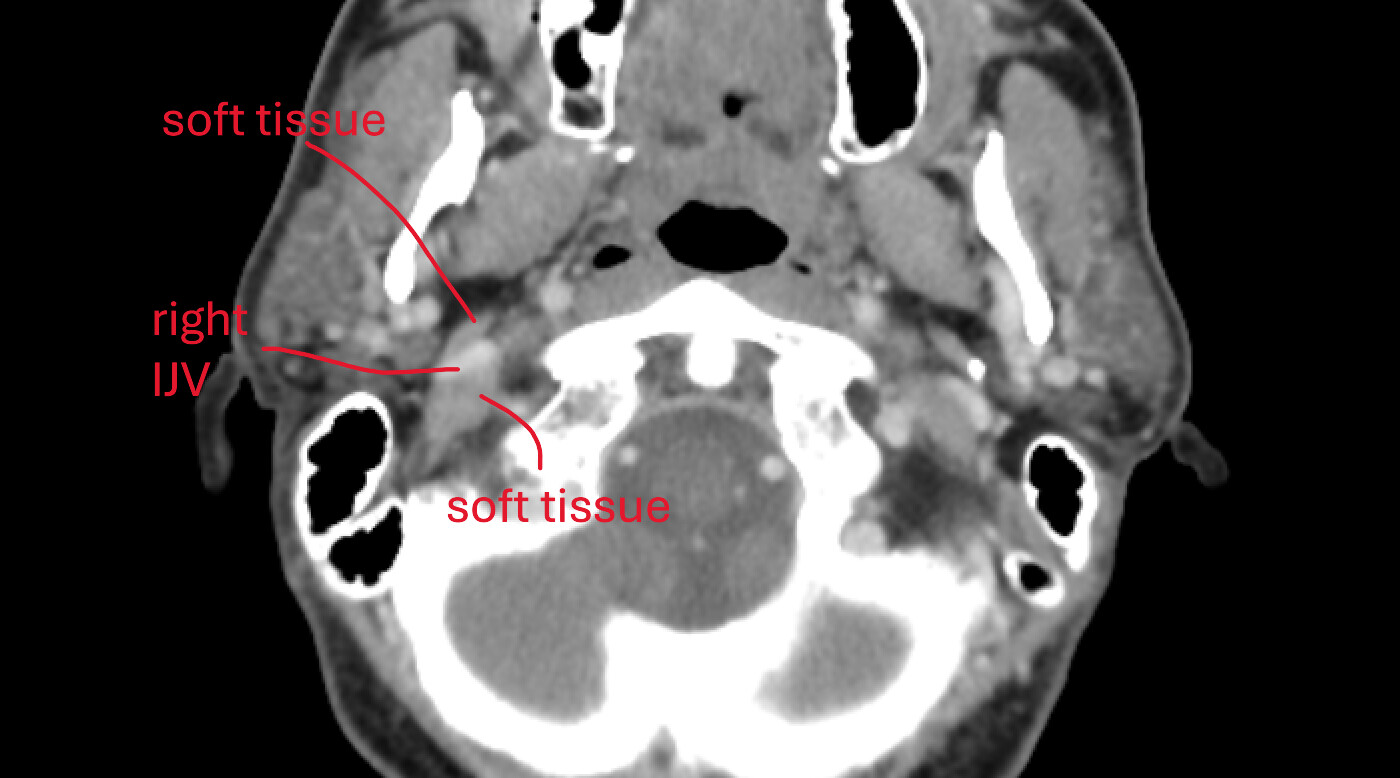

There is also sometimes a dull pain traveling down my throat and into the chest. Feels like it follows the path of the jugular. This is not always present.

It is quite lop-sided. Left side is quite low, right side is up. Not sure if that matters, but mentioning here. Pictures, below, will show this.

An animated gif with hyoid bone. Note the horns, left is quite lower than right.